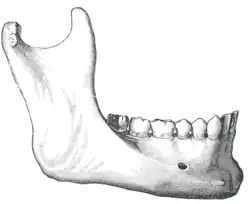

Abbau des Alveolarknochens

Der Abbau des Alveolarknochens beträgt im ersten Jahr nach dem Zahnverlust etwa 0,5 mm im Oberkiefer und 1,2 mm im Unterkiefer. In den Folgejahren beträgt der Abbau 0,1 mm im Oberkiefer und 0,4 mm im Unterkiefer, jeweils pro Jahr.[8] Der schnellere Abbau des Unterkieferknochens resultiert unter anderem daraus, dass die Auflagefläche für eine Prothese nur etwa halb so groß ist, wie die des Oberkiefers. Im Oberkiefer liegt die Prothese auch auf dem Gaumen auf. Dadurch sind die Belastungskräfte, die auf den Unterkiefer wirken, doppelt so groß wie im Oberkiefer. Daraus folgt, dass in der Regel nach etwa 20 Jahren Prothesentragedauer der Alveolarkamm des Unterkiefers vollkommen abgebaut und der Unterkiefer flach geworden ist. Er bietet dann keinen Halt mehr für eine Totalprothese.[2] In solchen Fällen kann durch verschiedene chirurgische Kieferknochenaufbauverfahren der Kiefer wieder rekonstruiert werden. Ein Halt der Prothese kann auch durch Implantate erreicht werden. Damit der Kieferabbau möglichst langsam vonstattengeht, muss die Prothese gut aufliegen. Dies muss durch regelmäßige, in ein- bis zweijährigem Abstand durchgeführte Unterfütterungen („Aufpolstern“) der Prothese erfolgen. Nach etwa fünf Jahren sollte eine Neuanfertigung erfolgen, da der Kunststoff im Laufe der Zeit spröde wird und dadurch die Bruchgefahr der Prothese bei der Kaubelastung steigt.

Beim sogenannten Normalbiss befinden sich die bukkalen (äußeren) Höcker der Oberkieferseitenzähne weiter außen, als die bukkalen Höcker der Unterkieferseitenzähne. Bei stark atrophierten Kiefern ist der zahnlose Unterkieferbogen regelmäßig größer als der Oberkieferzahnbogen. Häufig überkreuzen sich die Kieferkammbögen im Bereich der zweiten Prämolaren, woraus eine Aufstellung der Zähne im Kreuzbiss resultiert. Hierbei beißen die bukkalen Höcker der Unterkieferseitenzähne seitlich an den bukkalen Höckern der Oberkieferseitenzähne vorbei. Äußere begrenzende Strukturen für die Aufstellung der Seitenzähne sind im Oberkiefer die Crista zygomatikoalveolaris (Jochbein-Alveolarleiste) und im Unterkiefer die Linea obliqua mandibulae (schräge Unterkieferlinie).